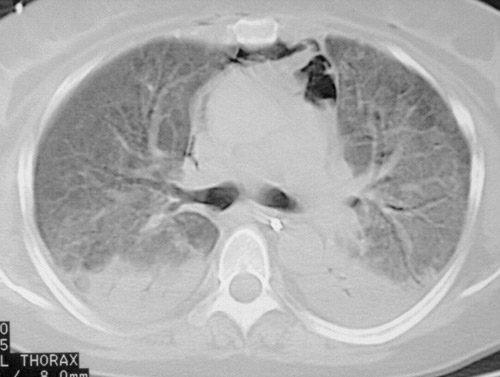

Компьютерная томография: двусторонние области альвеолярного помутнения

Острая интерстициальная пневмония начинается как банальная ОРВИ — с резкого подъема температуры и озноба. Внезапно появляется сильная одышка и приступообразный кашель. Болезнь развивается стремительно и быстро прогрессирует. У пациентов нарастают признаки респираторной недостаточности, отекают стенки альвеол, в них скапливается экссудат, возникает фиброзный процесс. Больным требуется ИВЛ до улучшения общего состояния. В противном случае человек погибает. Это самый опасный вид патологии с высоким процентом летальности.

КТ грудной клетки 42-летнего мужчины, больного ревматоидным артритом, с фиброзом легких (рубцеванием легких), вызванным неспецифической интерстициальной пневмонией

Неспецифическая пневмония протекает медленно. В легочной ткани появляются однородные воспалительные изменения, очаги фиброза, отек альвеолярных стенок, скопление внутри экссудата. Больные в течение нескольких лет мучаются от непроходящего кашля и постоянной одышки, усиливающейся по утрам, после физической нагрузки, подъема по лестнице. Эта форма патологии чаще возникает у пожилых лиц и злостных курильщиков. Неспецифическая пневмония может протекать бессимптомно. Пациенты страдают от общей слабости, упадка сил и прочих признаков астенизации. Клинические проявления со стороны дыхательной системы при этом отсутствуют.